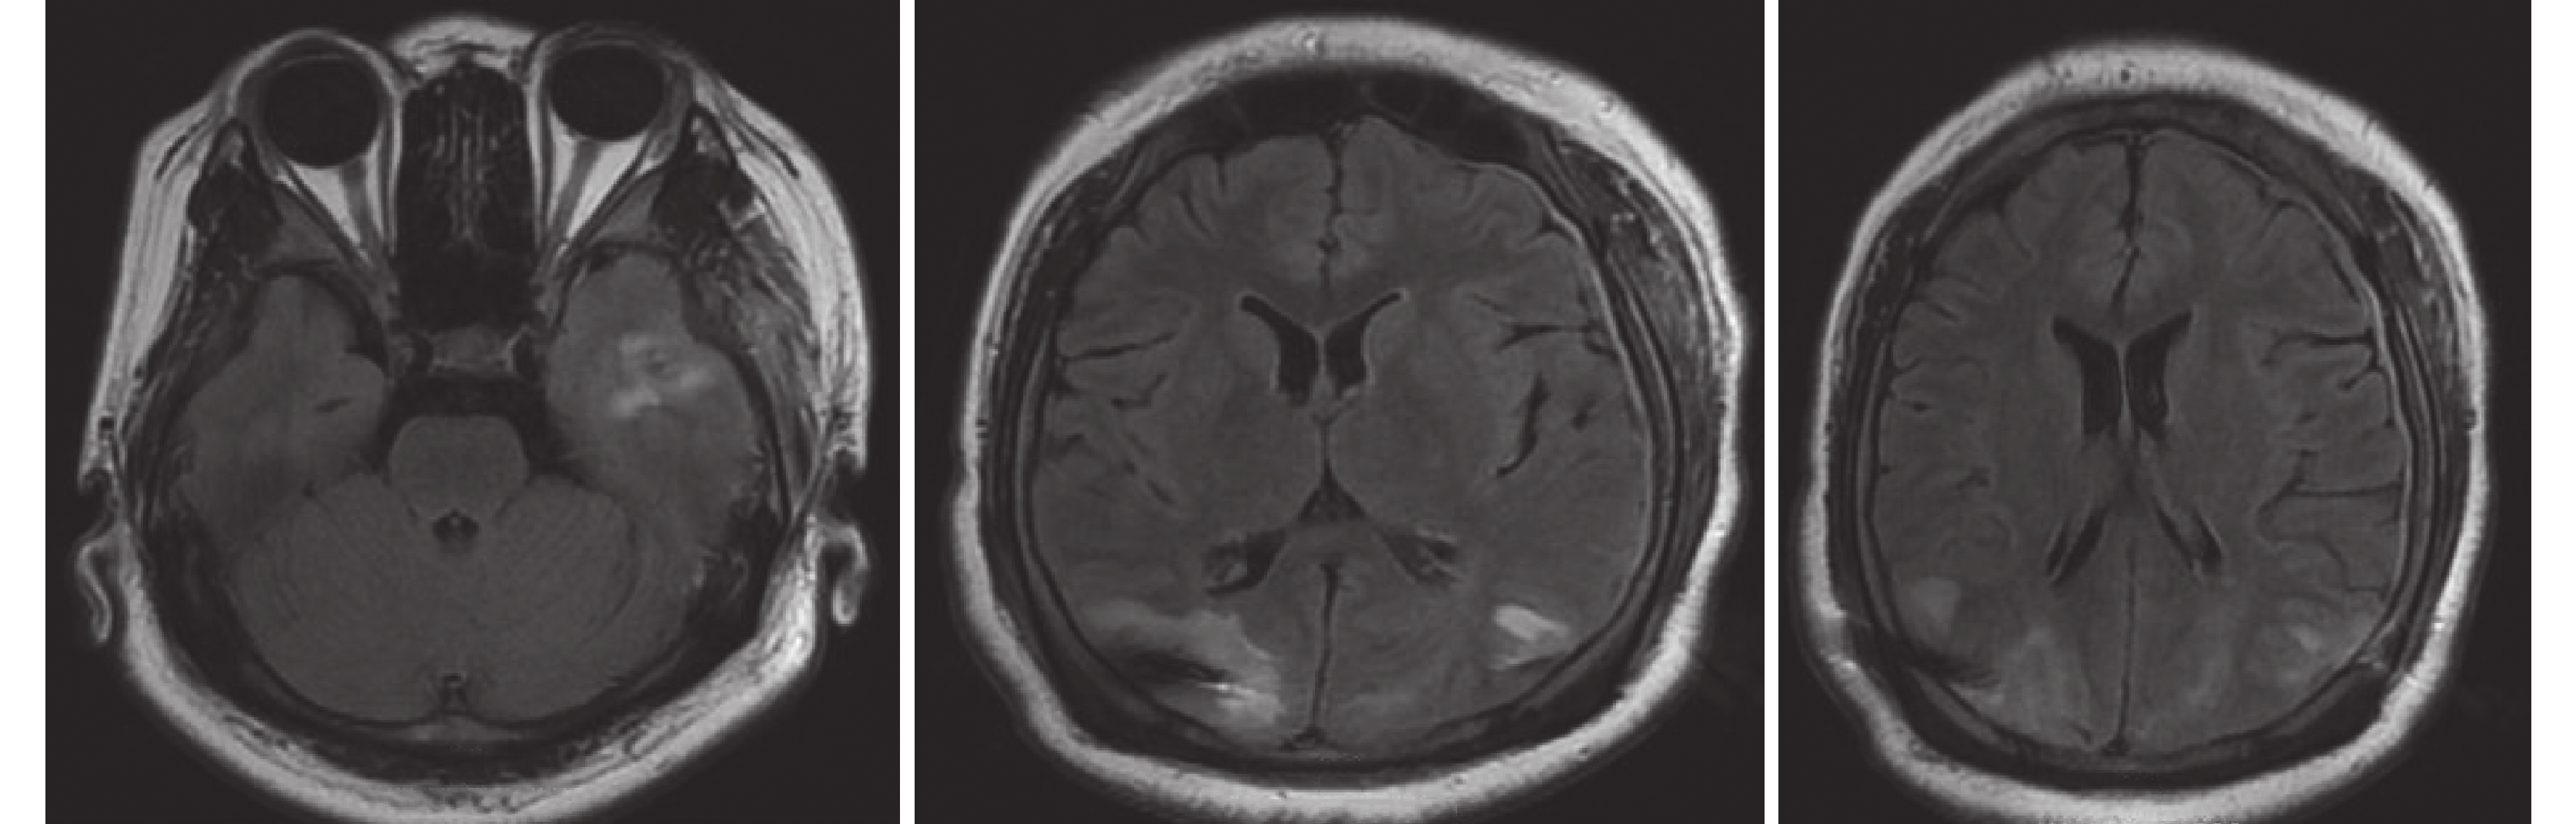

入院查體:神志清晰,精神不佳,對答可。雙瞳孔等大等圓,D=3 mm,光反射存在。左側眼瞼順目較右側少,鼓腮左側漏氣,示齒口角稍右偏。腦膜刺激征陰性。四肢可自主活動,肌力5級,肌張力正常。病理征陰性。視野缺損。入院后查頭部計算機斷層掃描(Computerized tomography,CT)及核磁共振(Magnetic resonance imaging,MRI)提示:雙側枕葉軟化灶。磁共振波譜(Magnetic resonance spectroscopy,MRS)檢查提示:左側海馬代謝較右側低(圖1)。長程視頻腦電圖(Videoelectroencephalography,VEEG)提示:發作間期右側額極、額區、左側額極、額區、顳區及額中線少量不同步中低波幅尖波散發出現,左枕區及后顳區可見部分低波幅尖波;視頻腦電圖監測發作期表現為愣神-咂嘴-右手摸索動作,持續約30 s后出現咳嗽,意識逐步好轉,但此時意識尚未完全恢復清楚,此后患者自行摘除網帽,事后不自知。發作期視頻腦電圖表現為剛開始在右枕(O2)、右后顳區(T6)出現低波幅快節律改變,波幅壓低,其后雙側額顳區出現高波幅慢波節律(圖2)。